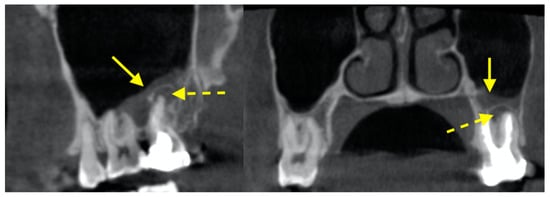

2.1. Posterior Superior Alveolar Artery (PSAA) and Lateral Wall Thickness